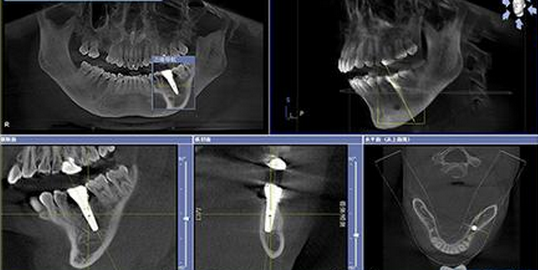

必須是齲齒,劇情講解:先是從(cong) 一個(ge) 小黑斑塊發展到然後隻剩下殘根。剛開始還能補牙,但是到了牙髓炎後就隻能做根管治療(比較痛苦)了,然後連牙根都保留不住了,隻能拔掉。(在拍片檢查的基礎上進行的)

拔牙後,需要花數千上萬(wan) 院的價(jia) 格做假牙,種植牙或者是做烤瓷牙以及活動假牙修複。假牙做好後悔了,覺得沒有真牙好用,但是真牙已經回不來了。

(種植牙片)